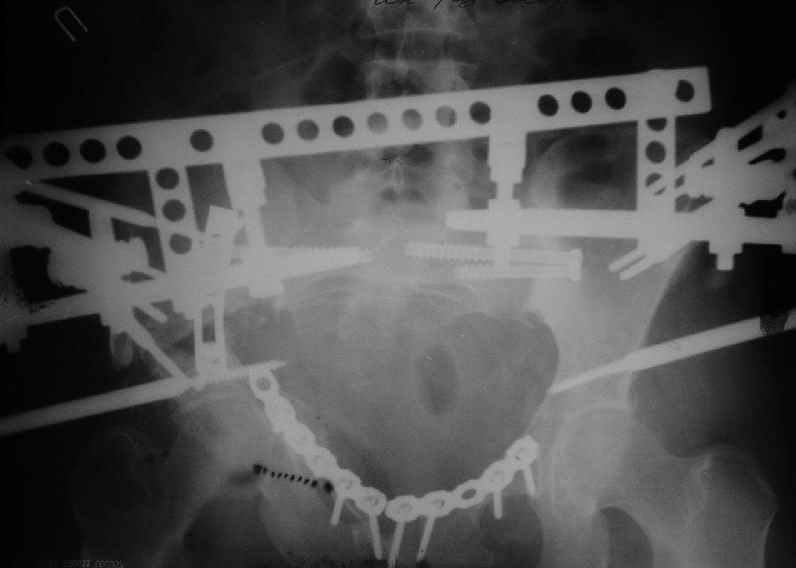

Уважаемые коллеги, вашему вниманию предлагается продолжеие истории лечения больной с двусторонней деформацией таза . Итак, 26.01.05 была выполнена остеотомия правой подвздошной кости, низведение правой вертлужной области, остеосинтез правой подвздошной кости пластиной, чрескостный остеосинтез аппаратом таз-бедро.  Снимок после первого этапа | После заживления раны и стабилизации общего состояния 22.02.05 была выполнена реконструкция переднего отдела таза, синтез лонных костей пластиной, опора с бедра демонтирована, выполнено введение илиосакральных винтов с обеих сторон. В настоящее время рана зажила первичным натяжением, больная ходит с двумя костылями без опоры на правую нижнюю конечность. С интересом ждем ваши комментарии.

Молодец, Максим ты еще раз доказал о виртуозности владения аппаратом, теперь надо удержать хорошо отрепонированные отломки, не спеша, нагрузку разрешить через 12 недель с момента операции, после рентгенологической консолидации.